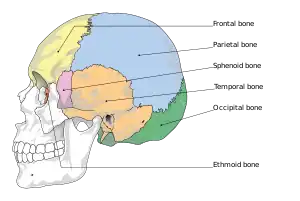

A basilar skull fracture typically requires a significant degree of trauma to occur.[1] It is defined as a fracture of one or more of the temporal, occipital, sphenoid, frontal or ethmoid bone.[1] Basilar skull fractures are divided into anterior fossa, middle fossa and posterior fossa fractures.[1] Facial fractures often also occur.[1] Diagnosis is typically by CT scan.[1]

Basilar skull fractures include breaks in the posterior skull base or anterior skull base. The former involve the occipital bone, temporal bone, and portions of the sphenoid bone; the latter, superior portions of the sphenoid and ethmoid bones. The temporal bone fracture is encountered in 75% of all basilar skull fractures and may be longitudinal, transverse or mixed, depending on the course of the fracture line in relation to the longitudinal axis of the pyramid.[5]